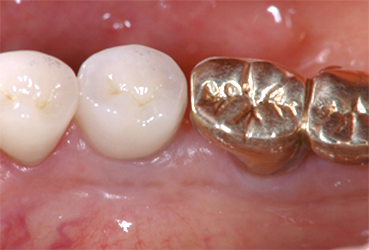

CASE

左下奥歯の虫歯が大きく被せ物が取れてきた右上の親知らずを 移植希望の30歳男性

BEFORE

金属の被せ物が取れて、歯の根の方まで虫歯が進行してしまっているため抜歯をしました。

初診時のレントゲン写真です。 向かって右から2番目。歯が割れているため、根のまわりが黒くなっています。 ここにカラー写真の向かって右から1番目の親知らずを移植します。

AFTER

移植し歯を固定ました。

移植から一週間後、根の治療をし土台を立て(写真左)、クラウンを被せました。(写真右)。